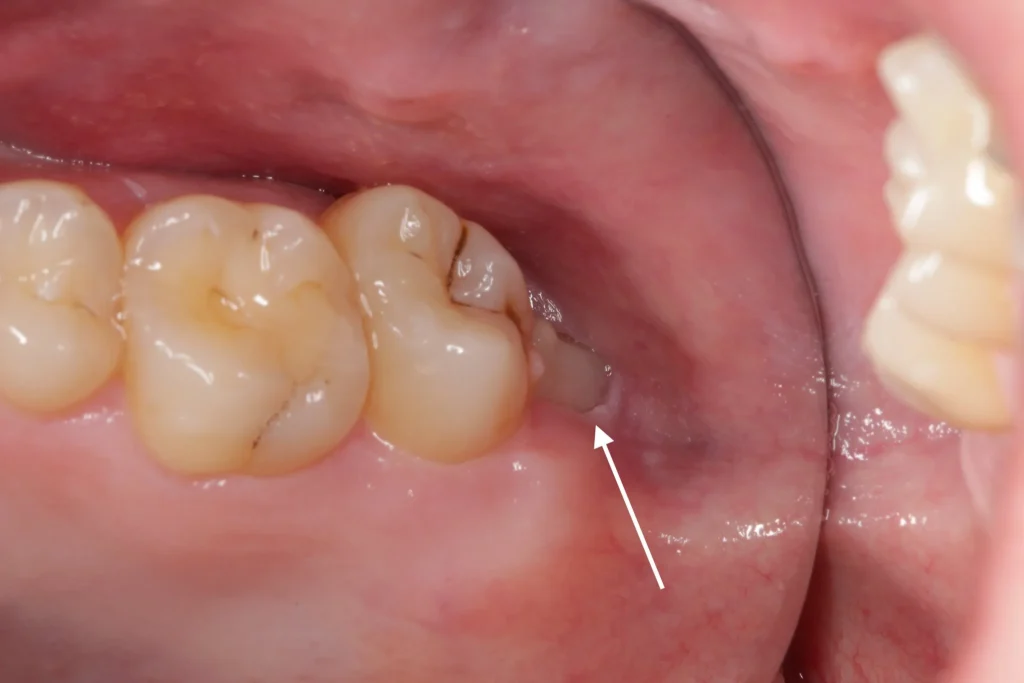

molarcan also lead to discomfort and discomfort in the surrounding teeth. - Infection and Gum Disease: When a wisdom tooth partially erupts, it creates an opening for

bacteriato enter around the tooth. This can lead to a localized infection called pericoronitis, which is characterized by redness, swelling, and pain. Over time, this can progress to more serious gum disease or periodontal disease. - Tooth Decay: Because they are so far back in the mouth, wisdom teeth are often difficult to clean. This makes them highly susceptible to tooth decay and the formation of decay. The hard-to-reach area can also be a breeding ground for germs and other contaminants.

- Damage to Neighboring Teeth: As an impacted wisdom tooth attempts to grow, its roots can press against the molar next to it, potentially causing damage to its structure and leading to

boneloss. - Cyst Formation: In rare cases, a

cystcan form around the impacted wisdom tooth. This fluid-filled sac can cause damage to the surrounding jawbone, teeth, and nerves. - Difficulty Chewing: In some cases, the improper growth of a wisdom tooth can interfere with normal chewing and bite alignment.